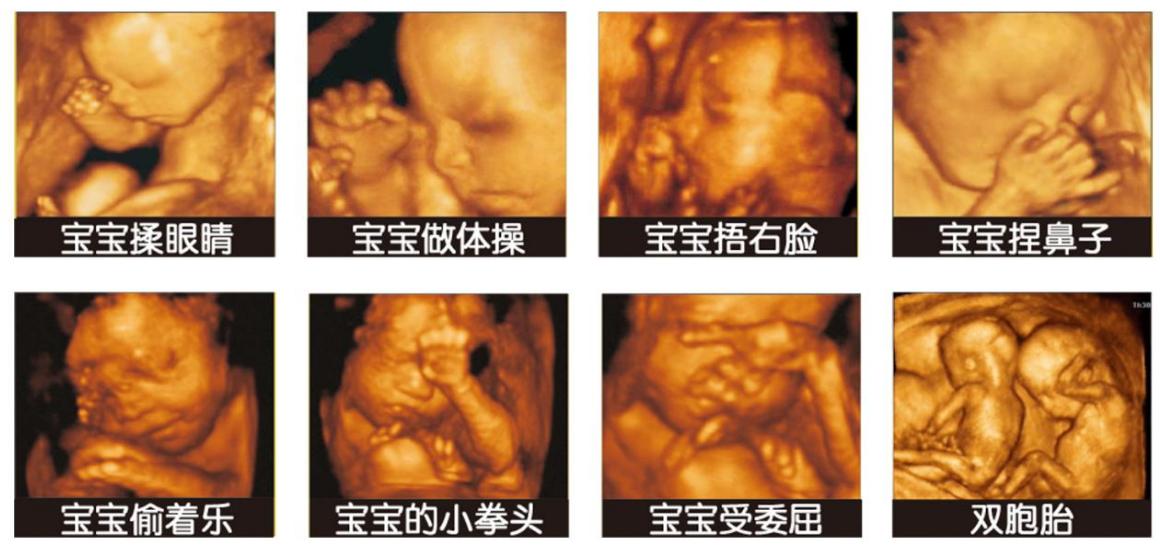

四维检查胎儿的生长发育情况、胎龄、筛查畸形

它能将胎儿神态、动作保存下来,可清晰地显示眼、鼻、口、下颔等状态,可协助医生直接对胎儿先天畸形进行诊断,包括表面畸形、内脏畸形和头面部畸形,能确定胎宝宝在孕妈咪子宫中的精确位置。